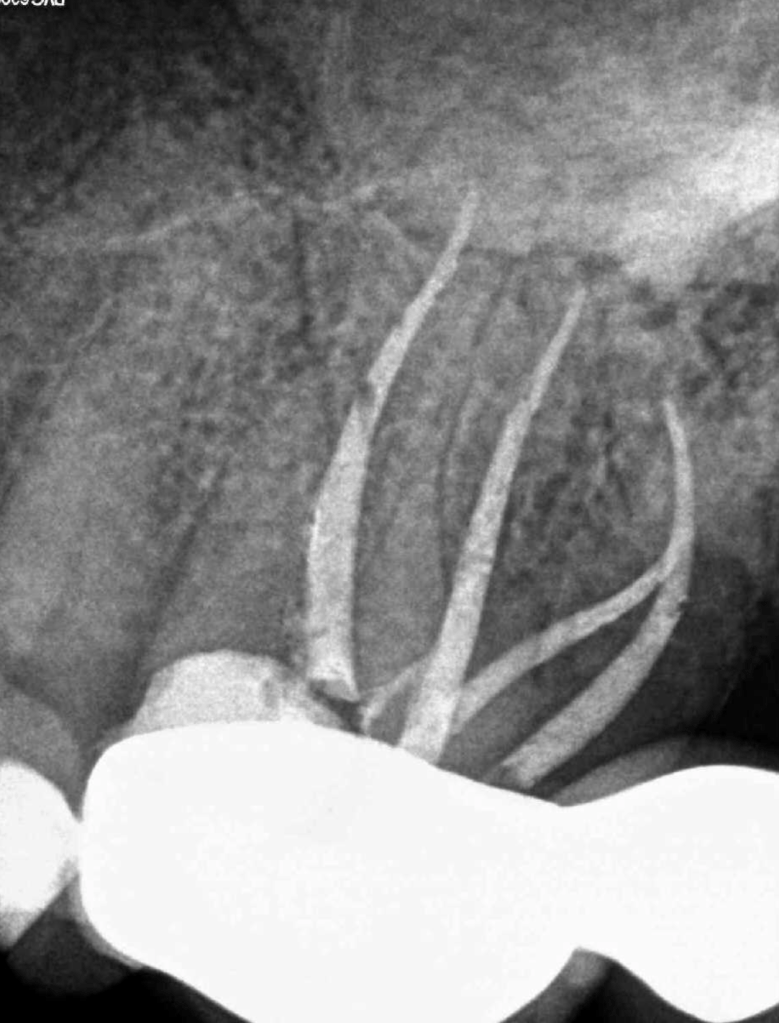

Molar superior anatomía compleja